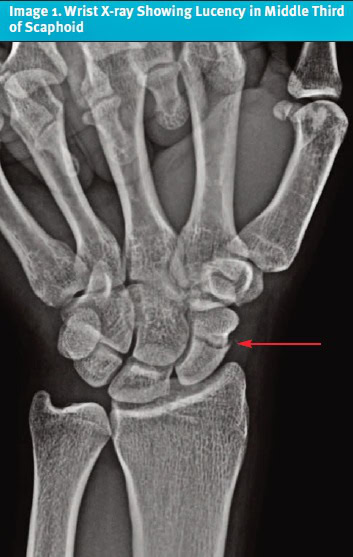

در میان ضایعات کبدی، همانژیومها یکی از شایعترین تودههای خوشخیم محسوب میشوند که اغلب بهصورت تصادفی شناسایی میشوند. در سونوگرافی، همانژیومها بهعنوان ضایعاتی هیپراکوئیک و همگن با حاشیه مشخص دیده میشوند. در تصویربرداری CT و MRI، این ضایعات در فاز شریانی تقویت محیطی ندولار و در فازهای 👀 بعدی پرشدن تدریجی نشان میدهند. تصویری از همانژیوم کبدی را در شکل بالا مشاهده میکنید که نمای اولتراسوند آن را بهعنوان یک ضایعه هیپراکوئیک نشان میدهد.